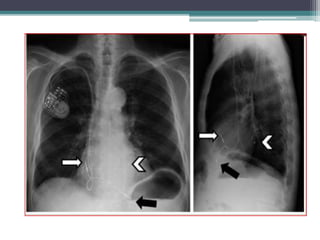

Lead Position

• LV lead location is probably one of the most

▫ Chest X-ray images (PA and lateral projection)